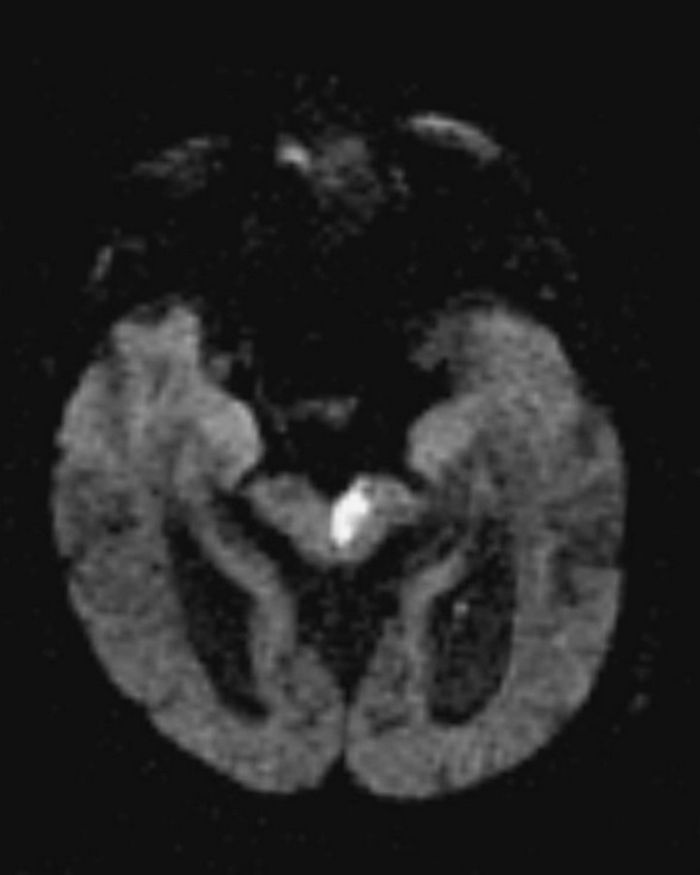

Stroke Syndrome:

“Dejerine and Roussy” Syndrome - Thalamic (on this case on the right). Infarction of sensory relay nucli due to occlusion of thalamogeniculates. These come from the PCA